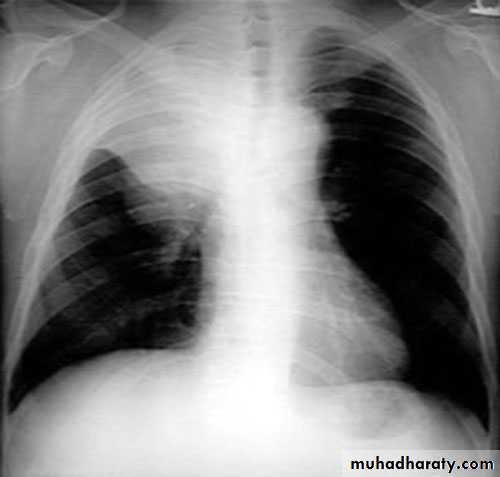

Pleural effusion ( free)